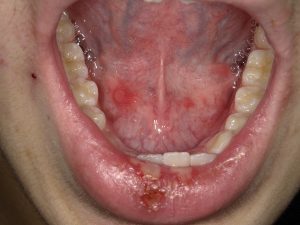

単純ヘルペスウイルスの感染により口唇や口腔粘膜、咽頭粘膜に強い痛みを伴うアフタ性の粘膜炎を起こします。発熱やリンパ節腫脹、嚥下障害も合併するケースが多く、重篤な状態となります。